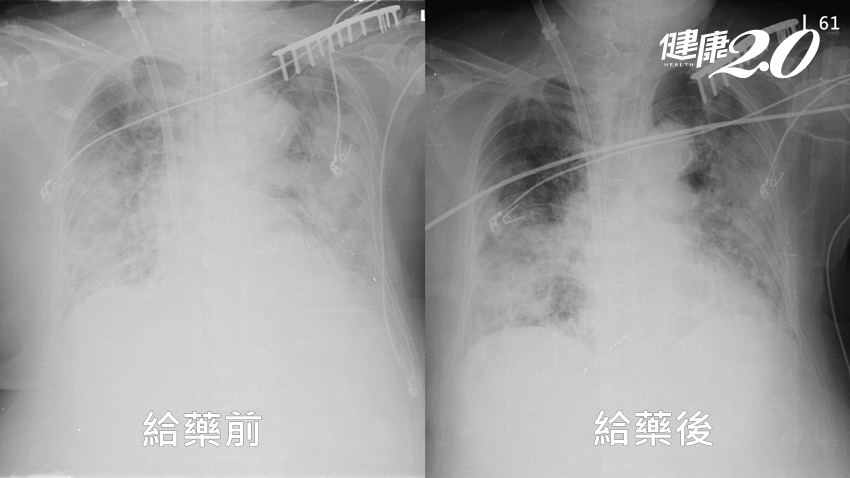

陳昭宇表示,乾燥症的診斷通常是由風濕免疫科確診或由其他科醫師懷疑轉診,確診之後可以使用健保藥物治療。眼睛的症狀主要使用局部藥物包含藥水及藥膏治療,嚴重的病人則可能需要做鼻淚管阻塞手術來改善症狀;嘴巴的症狀則有口服藥能改善,並由其他自費的保養產品可以輔助使用。